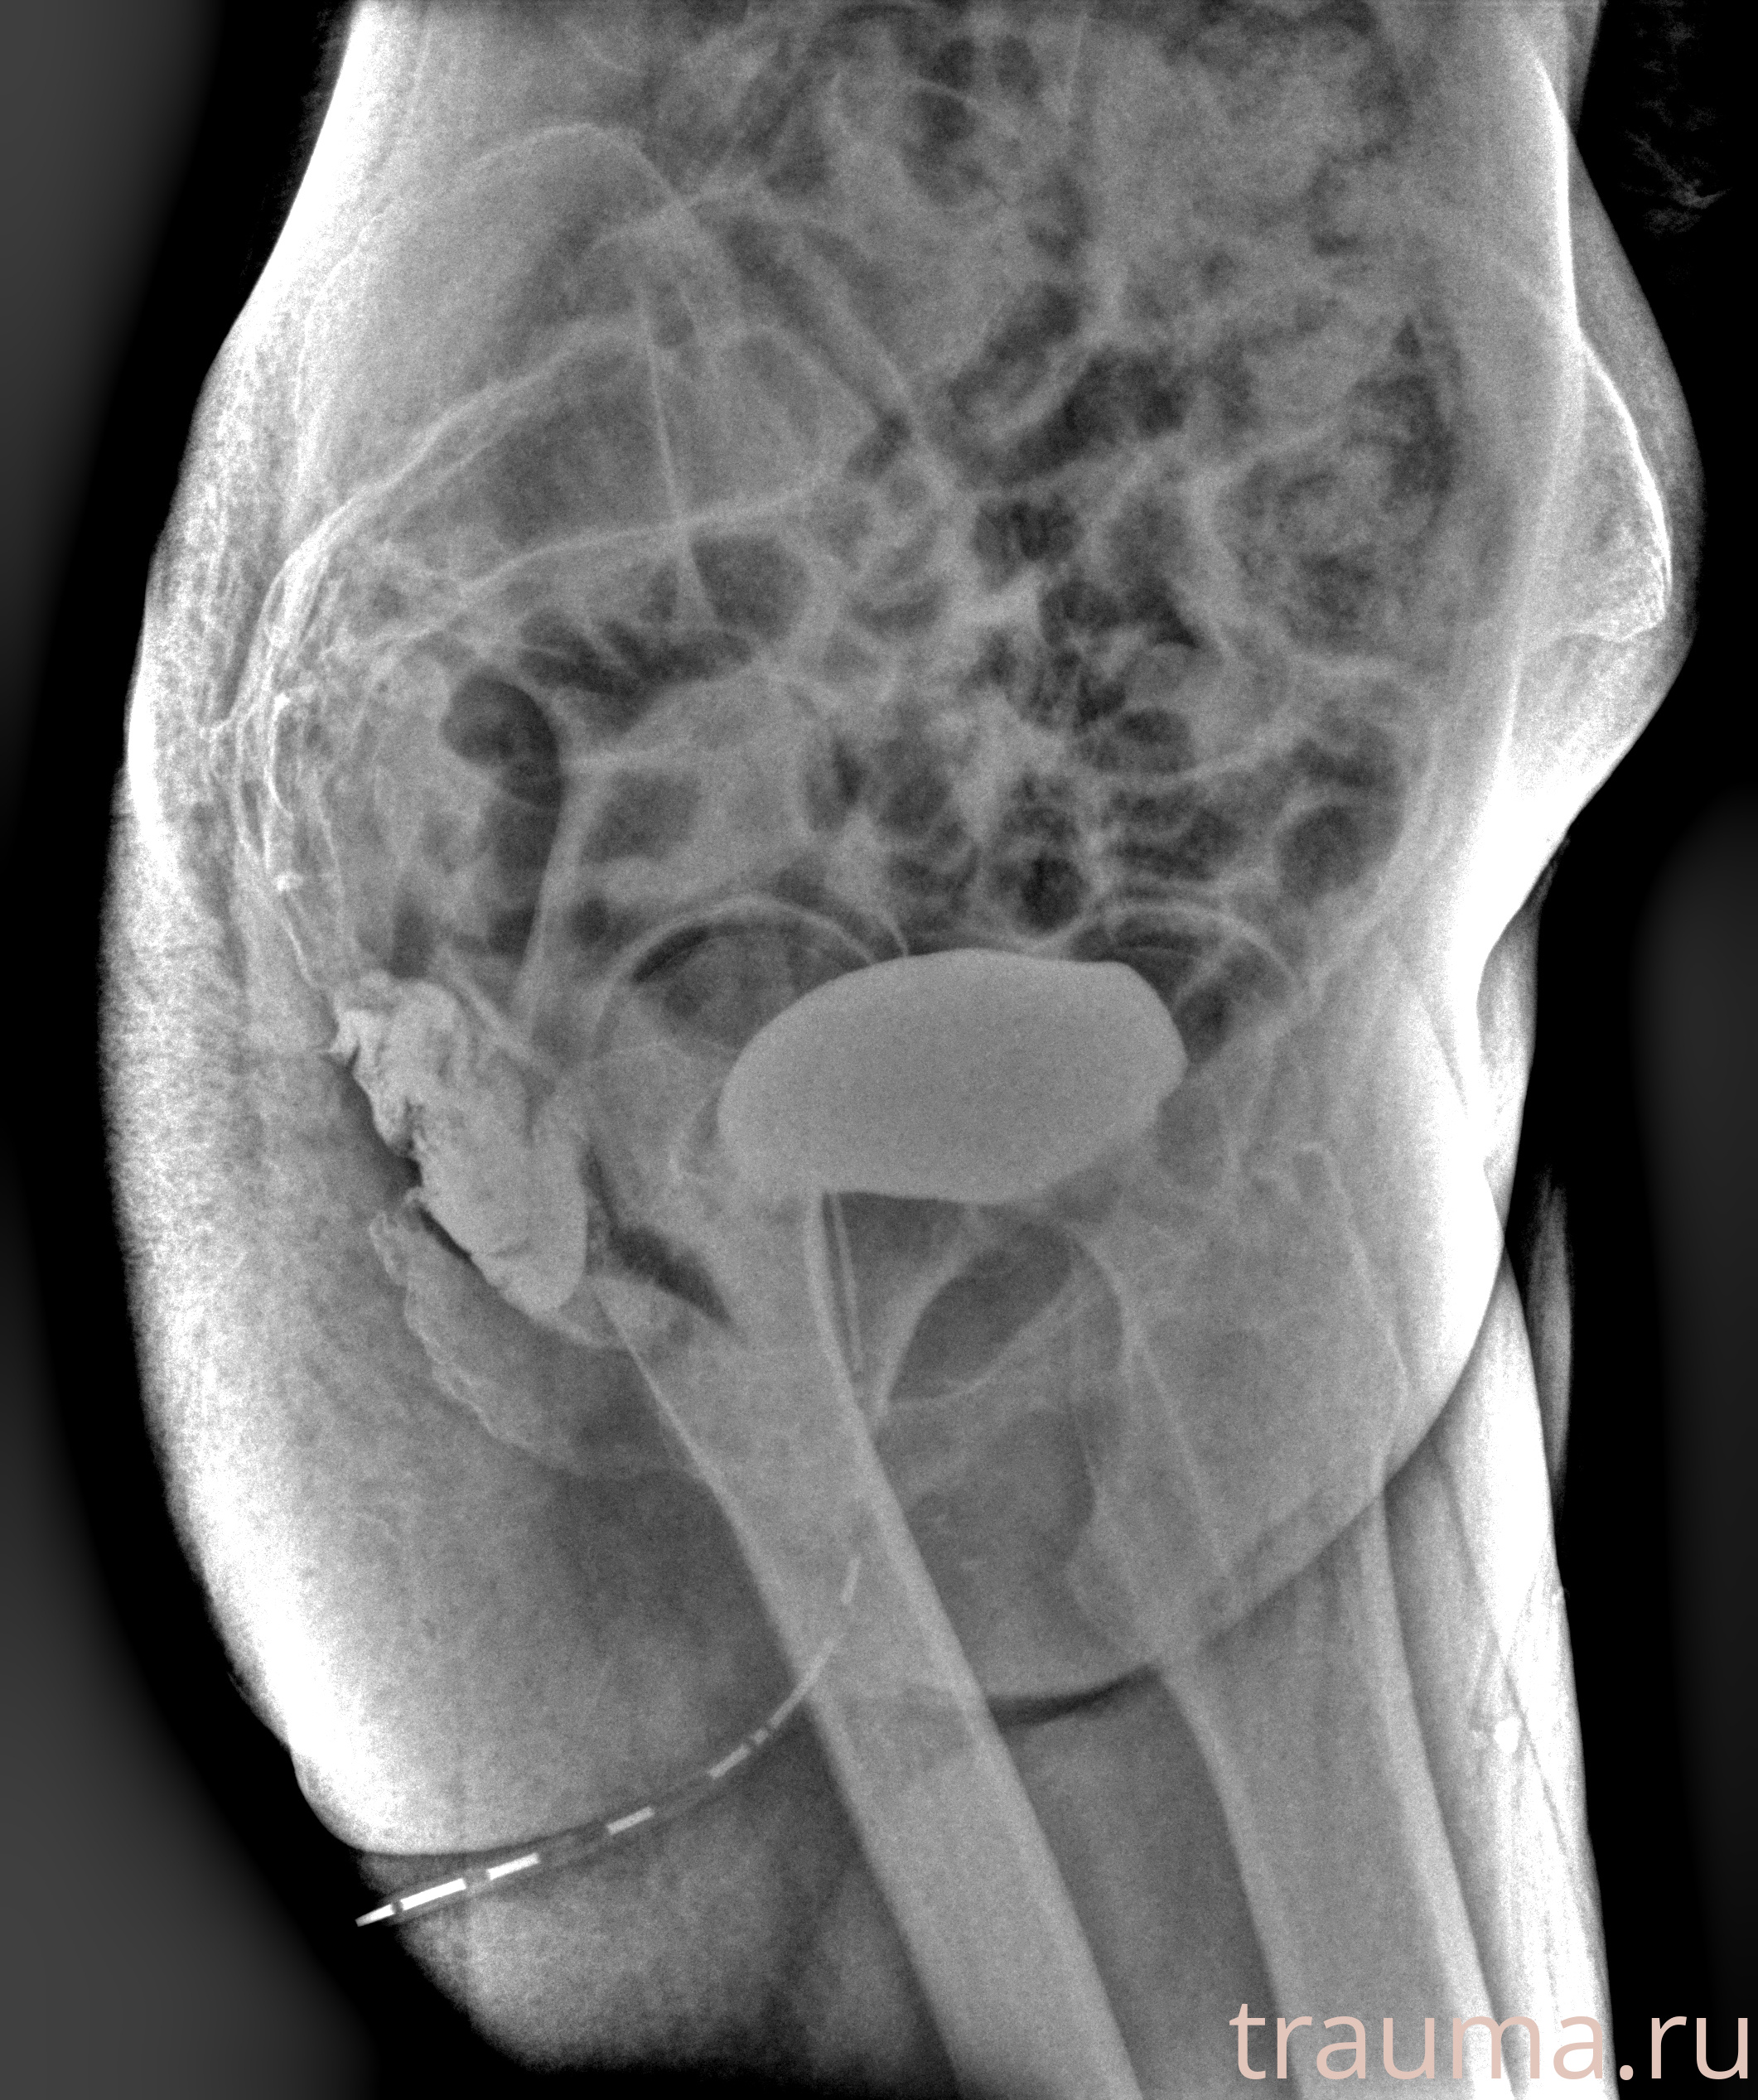

Рентген на дому: по вашему адресу приезжает врач-рентгенолог, травматолог-ортопед с мобильным рентгеновским аппаратом, проводит диагностику травмы или заболевания, делает необходимые рентгенограммы, дает рекомендации по дальнейшему лечению. Получить качественные снимки в домашних условиях возможно благодаря уникальной методике, разработанной МосРентген Центром для института  Склифосовского